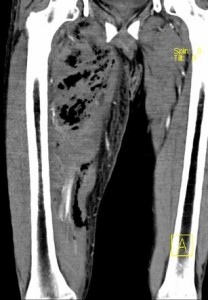

Los hallazgos que podemos encontrar en el TC son:

-Presencia de gas en partes blandas

-Engrosamiento asimétrico de las fascias con reticulación de la grasa adyacente

-Colecciones líquidas subfasciales

-Abcesos y linfadenopatías reactivas